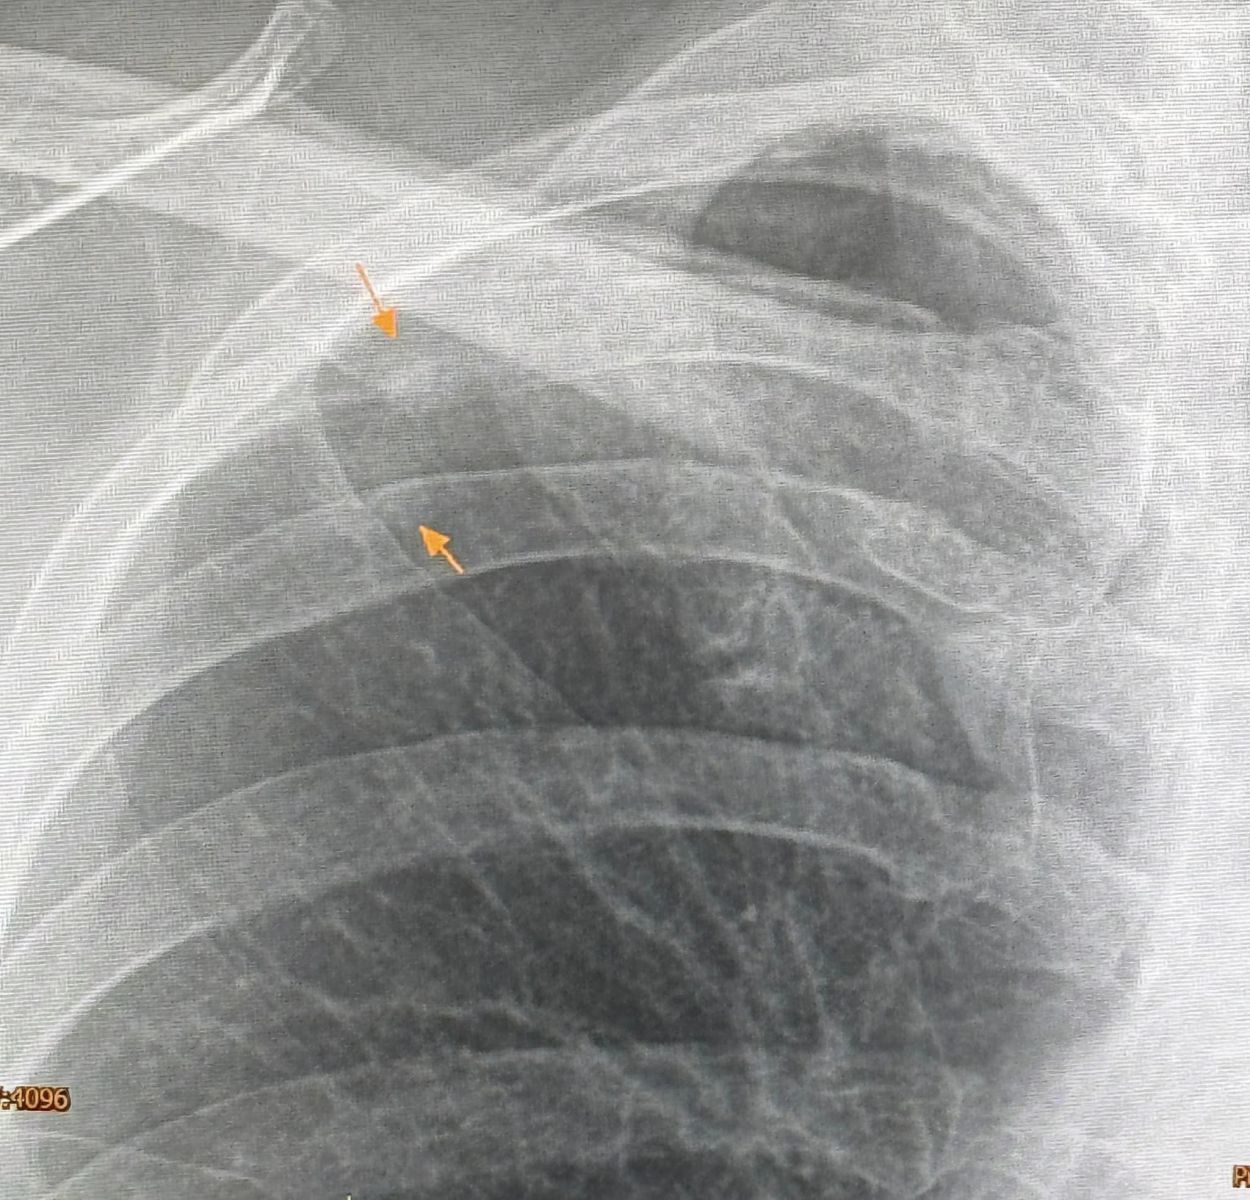

3 มิ.ย. 2567 นพ.มนูญ ลีเชวงวงศ์ ผู้เชี่ยวชาญด้านโรคระบบทางเดินหายใจ ได้โพสต์เฟซบุ๊กระบุว่า "ผู้ป่วยหญิงอายุ 52 ปี บ้านอยู่ กทม. ปกติแข็งแรงดี ไม่ไอ ไม่มีไข้ ไม่เบื่ออาหาร น้ำหนักไม่ลด ไม่ปวดหัว ไม่เคยสูบบุหรี่ ไม่มีโรคประจำตัว ไปตรวจร่างกายประจำปี วันที่ 12 พฤษภาคม 2567 เอกซเรย์ปอดพบก้อนเล็กๆเกิดขึ้นใหม่ที่ปอดขวากลีบบน เอกซเรย์ปอดก่อนหน้านั้น 1 ปีปกติ ทำคอมพิวเตอร์ปอดพบก้อนขนาด 0.9 × 0.9 × 1.7 เซนติเมตร เห็นโพรงอยู่ข้างในก้อนที่ปอดขวากลีบบน ตรวจเลือดไม่ติดเชื้อเอชไอวี ผู้ป่วยไปรับการผ่าตัดปอดเอาก้อนจากปอดขวากลีบบนออกที่โรงพยาบาลใกล้บ้านเมื่อวันที่ 22 พฤษภาคมเพราะสงสัยมะเร็งปอด ผลพยาธิวิทยาเป็นปอดอักเสบจากเชื้อราคริปโตคอคคัส ตรวจเลือดหาคริปโตคอคคัสแอนติเจนหลังผ่าตัด 4 วันให้ผลบวก titer 1:8 แพทย์เริ่มให้การรักษาด้วยยา fluconazole ผู้ป่วยมาขอคำแนะนำหลังจากนี้ควรทำอย่างไรต่อไป

ซักประวัติ มีนกพิราบอยู่แถวบ้านหลายตัว ให้อาหารนกพิราบประจำ ผู้ป่วยรายนี้หายใจสปอร์ของเชื้อราคริปโตคอคคัส นีโอฟอร์แมนส์ (Cryptococcus Neoformans) จากมูลนกพิราบเข้าไปในปอด ทำให้เกิดปอดอักเสบเป็นก้อนที่มีโพรงข้างใน โชคดีที่เชื้อราไม่ได้กระจายออกนอกปอดเนื่องจากร่างกายแข็งแรง มีภูมิคุ้มกันดี วางแผนให้ยาฆ่าเชื้อราฟลูโคนาโซลชนิดกินต่อไปประมาณ 6 เดือน แนะนำให้อยู่ห่าง และหลีกเลี่ยงให้อาหารนกพิราบ"